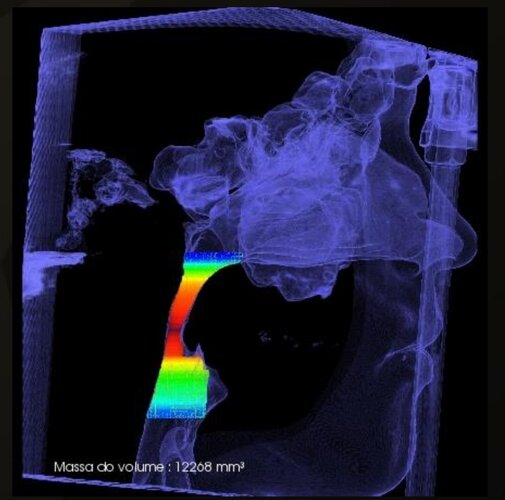

i have compressed airway (84mm smallest width), but doctors said i don't need surgery because i dont have sleep apnea.